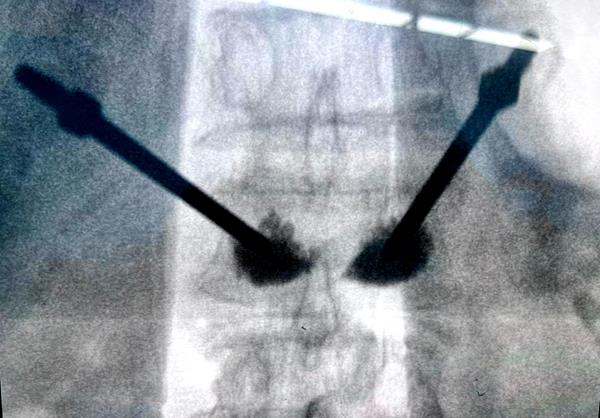

经皮椎体成形术(PVP)放射影像(微创手术)

经皮椎体成形术是一种微创手术,通过经皮穿刺向病变椎体内注入骨水泥(聚甲基丙烯酸甲酯),以增强椎体的强度和稳定性,快速缓解疼痛,恢复椎体部分高度。